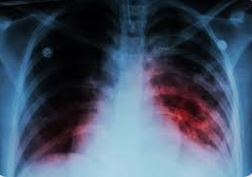

ਤਪਦਿਕ ਜਾਂ ਟੀਬੀ ਇੱਕ ਛੂਤ ਦੀ ਬਿਮਾਰੀ ਹੈ ਜੋ ਆਮ ਤੌਰ ‘ਤੇ ਫੇਫੜਿਆਂ ਨੂੰ ਪ੍ਰਭਾਵਿਤ ਕਰਦੀ ਹੈ ਅਤੇ ਇੱਕ ਬੈਕਟੀਰੀਆਂ ਦੁਆਰਾ ਹੋਣ ਵਾਲੀਆਂ ਹੋਰ ਬਿਮਾਰੀਆਂ ਦੇ ਮੁਕਾਬਲੇ ਦੁਨੀਆ ਭਰ ਵਿੱਚ ਦੂਜਾ ਸਭ ਤੋਂ ਵੱਡਾ ਕਾਤਲ ਹੈ।

ਜਦੋਂ ਕਿ ਮਨੁੱਖਾਂ ਵਿੱਚ ਸਭ ਤੋਂ ਵੱਧ ਪ੍ਰਭਾਵਿਤ ਥਾਵਾਂ ਫੇਫੜੇ ਹਨ,ਟੀਬੀ ਹੱਡੀਆਂ ਵਿੱਚ ਵੀ ਹੋ ਸਕਦੀ ਹੈ,ਖਾਸ ਕਰਕੇ ਰੀੜ੍ਹ ਦੀ ਹੱਡੀ ਵਿੱਚ l ਟੀਬੀ ਦੀਆਂ ਹੋਰ ਆਮ thavaਥਾਵਾਂ ਵਿੱਚ ਲਿੰਫ ਨੋਡਸ,ਦਿਮਾਗ ਅਤੇ ਗੁਰਦੇ ਆਦਿ ਸ਼ਾਮਲ ਹਨ। ਅਸਲ ਵਿੱਚ, ਕੋਈ ਵੀ ਅਜਿਹਾ ਅੰਗ ਨਹੀਂ ਹੈ ਜਿਸ ਨੂੰ ਟੀ.ਬੀ ਦੀ ਮਾਰ ਨਹੀਂ ਪੈ ਸਕਦੀ । ਹਾਲਾਂਕਿ, ਅਕਸਰ ਕਿਤਾਬਾਂ ਅਤੇ ਫਿਲਮਾਂ ਵਿੱਚ ਇੱਕ ਭਿਆਨਕ ਬਿਮਾਰੀ ਵਜੋਂ ਦਰਸਾਇਆ ਗਿਆ ਹੈ, ਤਪਦਿਕ ਅੱਜ ਇੱਕ ਬਹੁਤ ਹੀ ਇਲਾਜਯੋਗ ਬਿਮਾਰੀ ਹੈ ਜਿਸ ਬਾਰੇ ਜਾਗਰੂਕਤਾ ਦੀ ਲੋੜ ਹੈ।

ਤਪਦਿਕ (ਟੀਬੀ) ਭਾਰਤ ਵਿੱਚ ਇੱਕ ਬਹੁਤ ਹੀ ਆਮ ਇਨਫੈਕਸ਼ਨ ਹੈ ਜੋ ਇੱਕ ਬਹੁਤ ਜ਼ਿਆਦਾ ਛੂਤ ਵਾਲੀ ਬਿਮਾਰੀ ਹੈ l ਇਹ ਬੈਕਟੀਰੀਆ (ਆਮ ਤੌਰ ‘ਤੇ ਮਾਈਕੋਬੈਕਟੀਰੀਅਮ ਟੀਬੀ) ਦੇ ਕਾਰਨ ਹੁੰਦੀ ਹੈ ਅਤੇ ਸਭ ਤੋਂ ਵੱਧ ਫੇਫੜਿਆਂ ਨੂੰ ਪ੍ਰਭਾਵਿਤ ਕਰਦੀ ਹੈ।

ਇੱਕ ਸਰਗਰਮ ਲਾਗ ਦੇ ਮਾਮਲੇ ਵਿੱਚ, ਲੱਛਣ ਪ੍ਰਭਾਵਿਤ ਅੰਗ ਦੇ ਅਨੁਸਾਰ ਵੱਖ-ਵੱਖ ਹੋ ਸਕਦੇ ਹਨ। ਜੇਕਰ ਫੇਫੜੇ ਪ੍ਰਭਾਵਿਤ ਹੁੰਦੇ ਹਨ, ਤਾਂ ਲੱਛਣ ਹਨ: